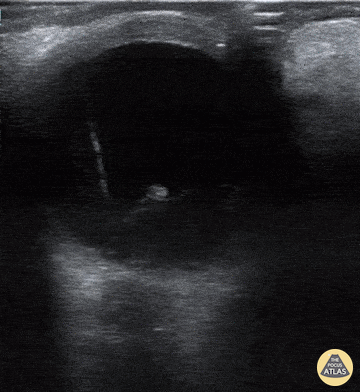

A 70-year-old man presented with loss of vision to his right eye (hand motion and light perception). He takes warfarin and has diabetes. Monocular vision loss triggered a POCUS that revealed a hazy echogenic substance (consistent with blood) seen best when patient activates extra-ocular muscle movements. Also note the associated bright linear structure within one portion of the bleed, the hyaloid membrane. This patient was subsequently assessed by the Eye Hospital and diagnosed with vitreous hemorrhage due to proliferative diabetic retinopathy. Peter Cheng